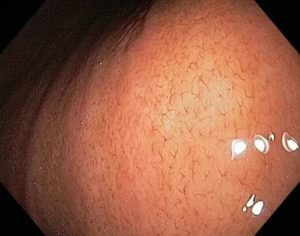

Слизистая оболочка (ее также называют мукозной оболочкой – от лат. «mucosa») состоит из соединительной ткани и в норме имеет светло-розовый цвет. При эндоскопическом обследовании желудка здоровая слизистая способна отражать блики оптического устройства.

Гиперемированная слизистая, в которой скопилось большое количество крови, выглядит отекшей. Возможно появление светло-серых очагов с выраженным сосудистым рисунком, на некоторых участках слизистая может приобретать синюшный и мраморный оттенок. Структура – рыхлая, пастозная (тестообразная). Эластичность снижена.

Опытный и квалифицированный специалист сразу распознает отечную и покрасневшую слизистую оболочку, так как в норме внутренний слой желудка должен иметь бледно-розовый цвет и прозрачную слизь. Если есть хоть какие-то отклонения от этой нормы, значит, выставляется предварительный диагноз гиперемии слизистой желудка.

В норме слизистая желудка имеет светло-розовый цвет, который становится ярче ближе к пилорическому отделу. У некоторых пациентов они желтоватого оттенка, что не является патологией.

Во время осмотра эпителий отражает свет эндоскопа, поэтому она выглядит блестящей. Многочисленные складки слизистой имеют толщину 6-10 мм. Их размер постепенно увеличивается ближе к антральному отделу.

При введении в полость желудка воздуха, складки слизистой разглаживаются, и это позволяет осмотреть всю поверхность.